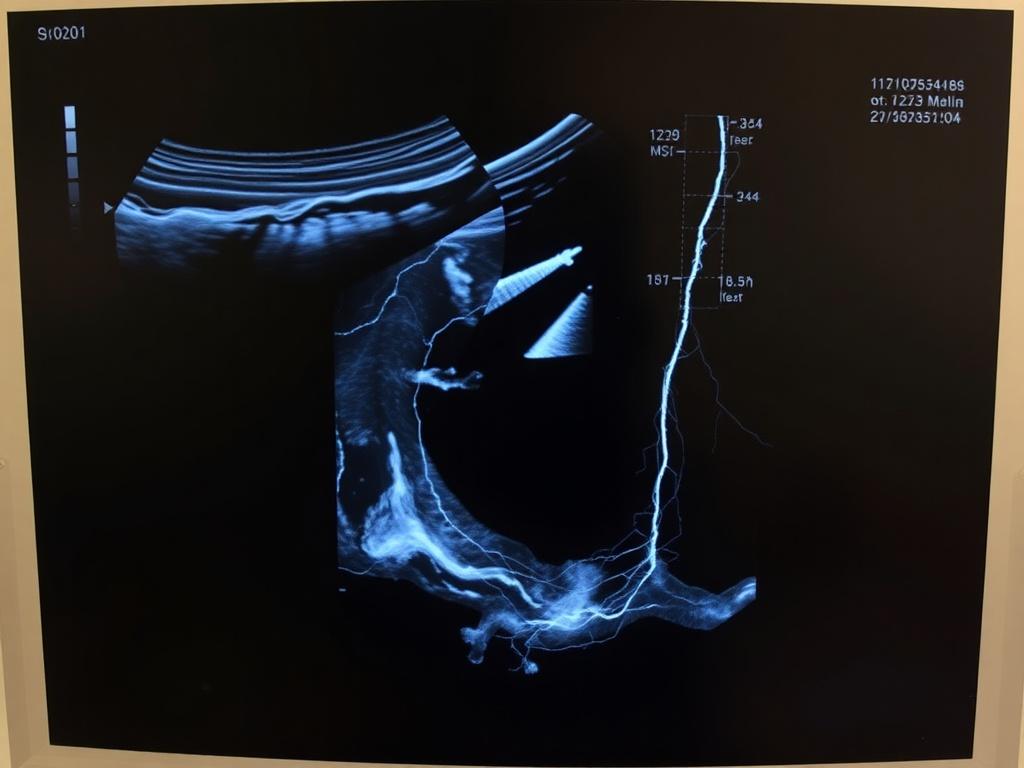

В основе лежит тот же принцип, что и в любом УЗИ — отражение звуковых волн от неоднородностей ткани. Для вен используют специально настраиваемые датчики и несколько режимов: серошкальный — для оценки структуры и компрессии сосуда, цветовой допплер — для визуализации направления и наличия кровотока, и допплеровский спектр — для качественной оценки скорости и характера потока. Часто говорят «дуплексное сканирование» — это сочетание визуального изображения и допплера. Такой подход позволяет не только увидеть, есть ли тромб внутри вены, но и понять, как кровь движется и куда.

При оценке вен ключевые признаки, на которые обращают внимание, — это проходимость просвета, компрессируемость, эхогенность содержимого, наличие и направление потока, а также расширение или деформация вены. Нормальная вена легко сдавливается, в ней виден свободный поток крови цветом допплера. Тромб в острой фазе обычно выглядит как анэхогенное или смешанного типа образование, которое не позволяет стенкам смыкаться и блокирует поток.

Со временем тромб становится плотнее и эхогенность увеличивается — это признак старения процесса и возможной реканализации. При хронической венозной недостаточности основной находкой будет рефлюкс — обратный ток крови через устья вен или перфоранты. Варикозные расширения выглядят как извилистые, расширенные подкожные вены с патологическим током.